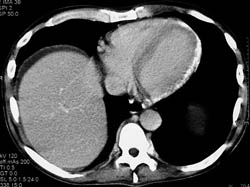

Pericardial Calcification